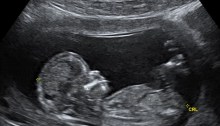

Pro-Life Letter to the Editor, 2016 Edition

Every year for the January 22nd anniversary of the Supreme Court decision that legalized abortion in this country in 1973 I write a pro-life letter to the editor for our local newspaper. Some years the newspaper prints it, some years they don’t. This was a year that, for no apparent reason, they did not print…